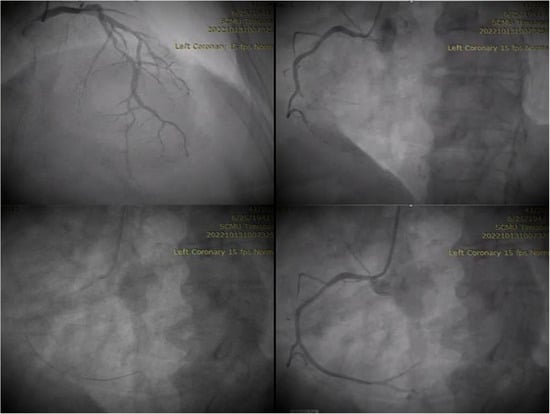

2. Case Presentation